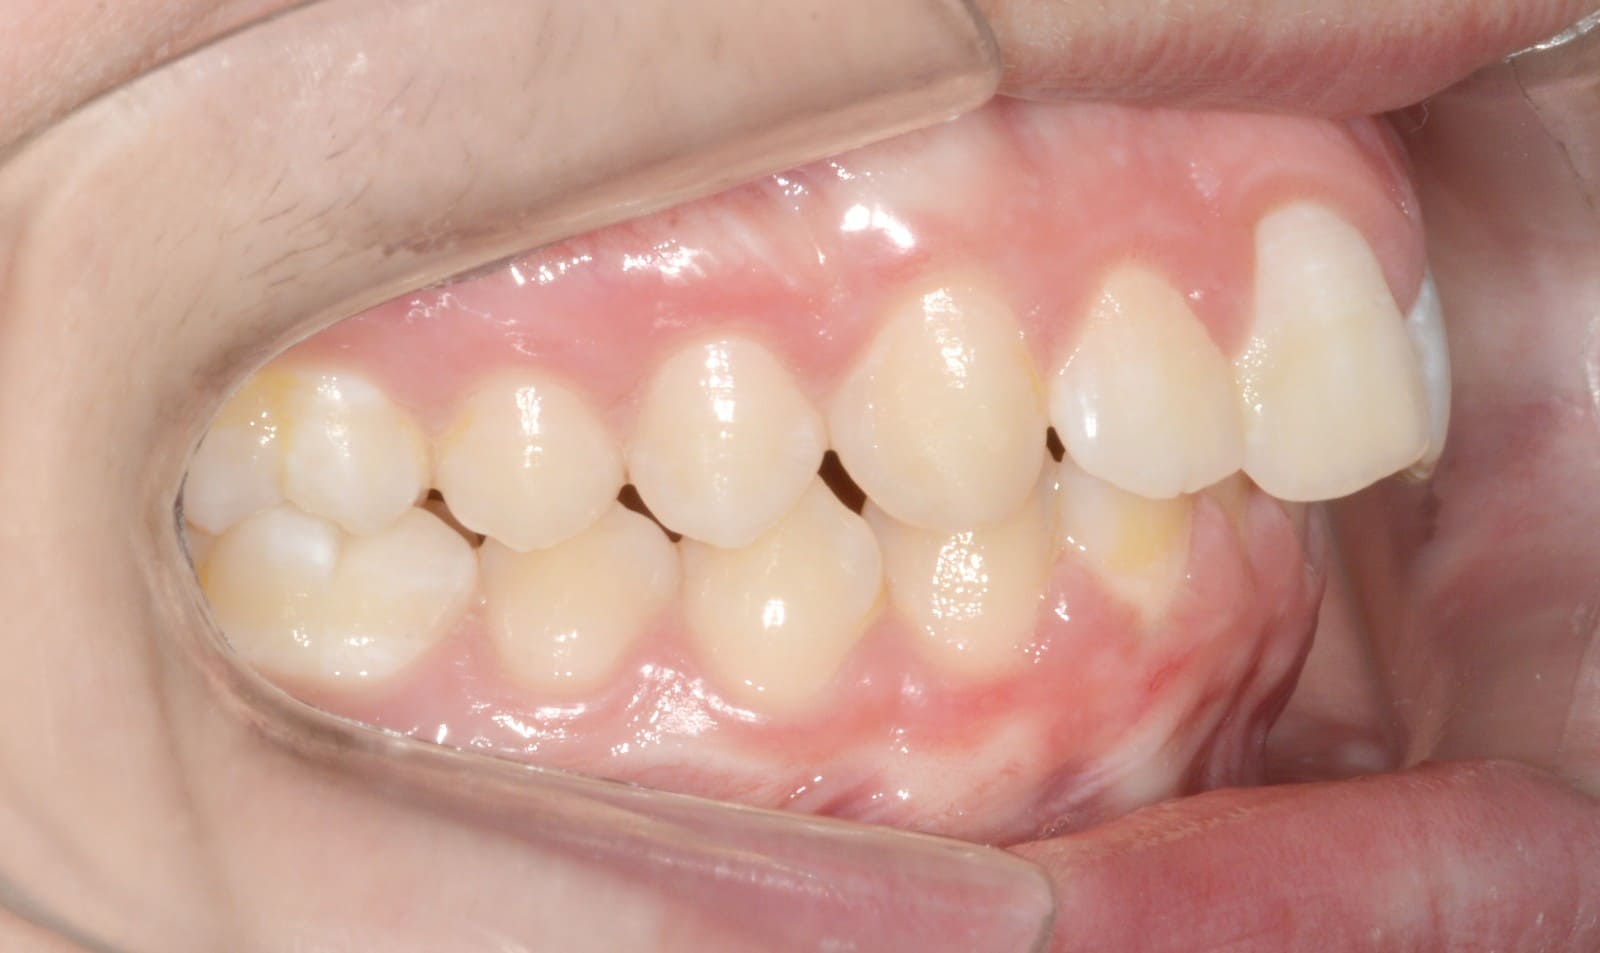

Results achieved

- Class I relationship achieved

- Functional canine guidance on both sides

- Normal overjet and overbite achieved

- Significant improvement of overbite

- Significant improvement of overjet

- Proper axial inclination of incisors

- Curve of Spee leveled

- Arches aligned and coordinated

- Arch form improved

- Aesthetic smile line was achieved

- All treatment goals were achieved case

- Harmonic arches were achieved